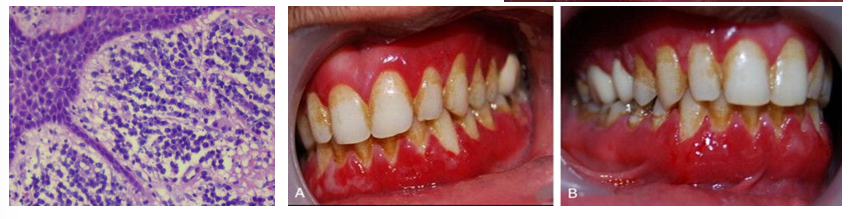

plasma cell gingivitis

-allergic rxn to various allergens including components of chewing gum, herbal toothpaste, mint candy, peppers used for cooking, etc.

-rapid onset of sore mouth, intensified by dentrifices and hot/spicy foods

-entire gingiva becomes diffusely enlarged with bright erythema and loss of normal stippling

-edentulous areas exhibit less intense change

-topical placement of allergenic material → localized gingival and vestibular alteration

plasma cell gingivitis diagnosis and treatment

-dx: biopsy- plasma cell infiltrate in lamina propria, r/o neoplasm, find possible allergens- complete dietary history/records of everything taken orally, eliminate potential allergen and see if condition improves, allergy testing

-treatment: topical or systemic immunosuppressive medications if failed to identify the allergen (variable success), in spite of all evaluations and therapeutic interventions, some patients do not respond to treatment and no cause for disease can be identified